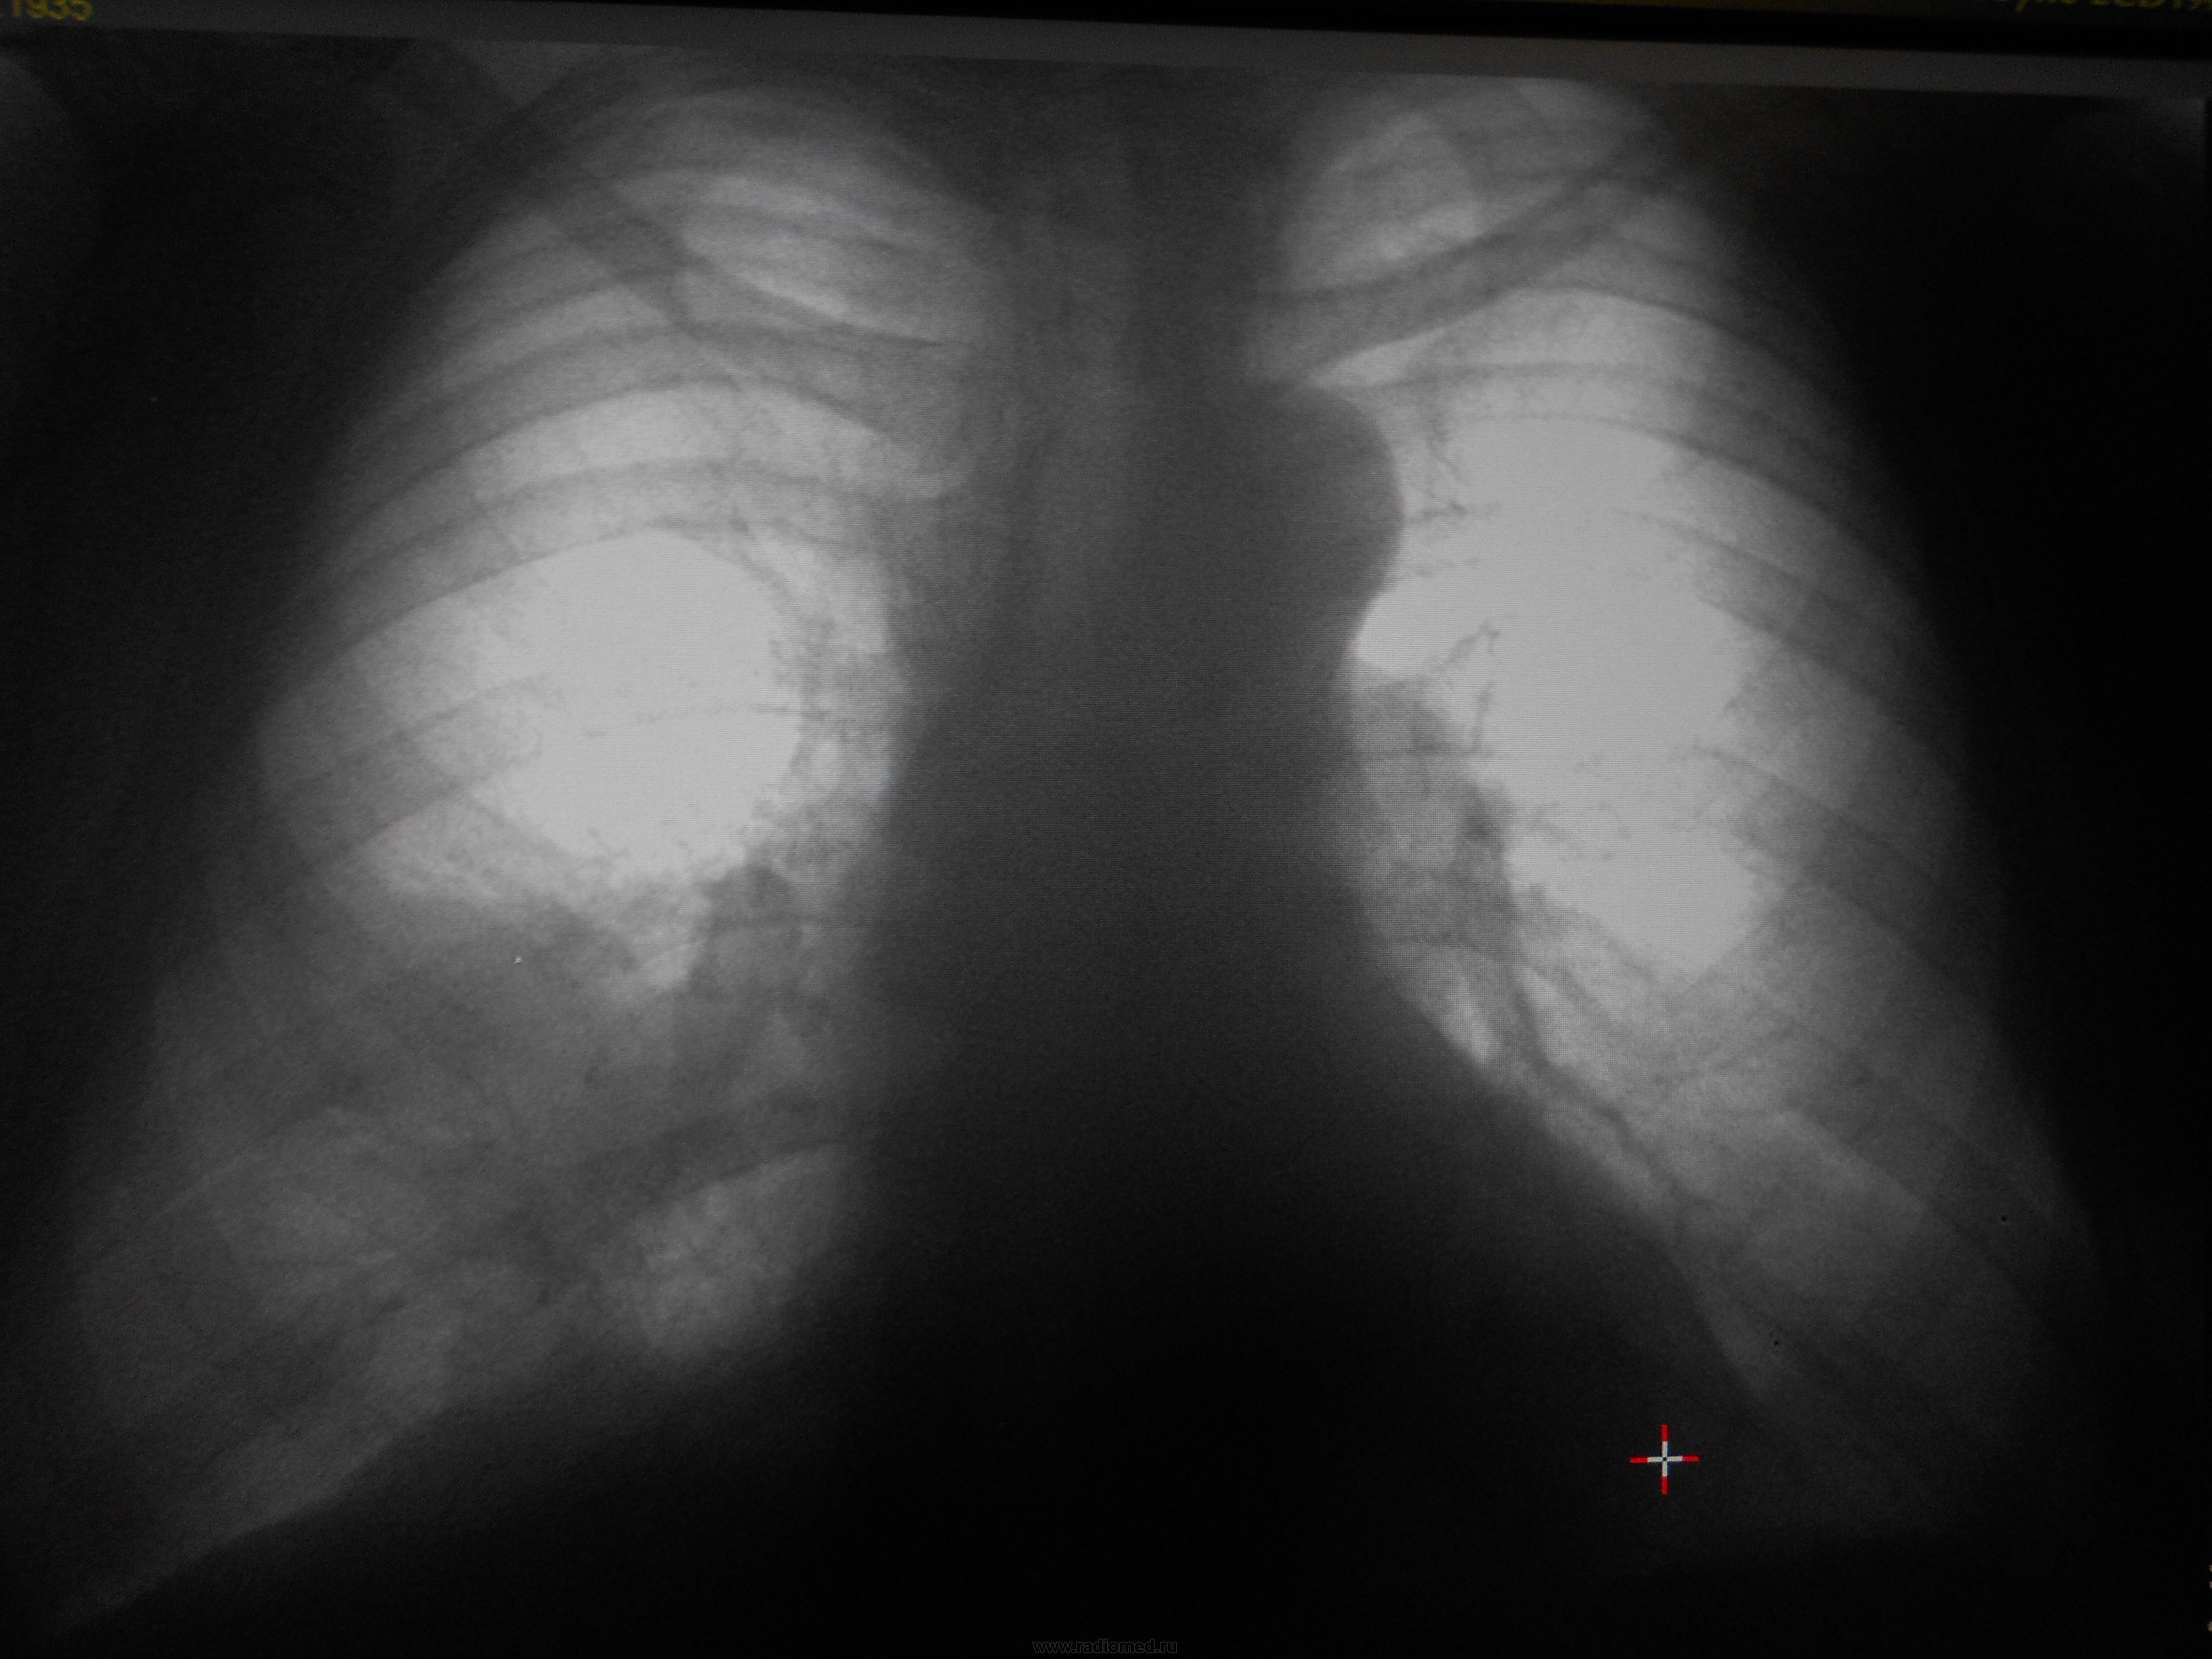

Бабуля, 1935 года. Направлена на ФЛГ с диагнозом хронический бронхит. Беспокоили повышение температуры до 38 градусов, слабость, кашель. На ФЛГ 2.10 выявлены изменения, бабушка лечится антибиотками и вроде ей становится лучше. На контроль приходит 18.10 - без динамики, направлена к пульмонологу. Пульмонолог присылает обратно к нам, чтобы мы сделали нормальные снимки, а не распечатку. Сегодняшние снимки - без динамики. На данный момент беспокоят слабость, кашель. До того как заболела говорит о частых пневмониях, периодических подъемах температуры до 38 на один-два дня в течение нескольких месяцев. О чем тут можно думать?

18.10

22.11

По-моему, очень похоже на классический среднедолевой синдром с гиповентиляцией.

О периферическом. Круглая тень где-то в области S10 намекает.

Пульмонолог написала среднедолевой синдром, рекомендовала СКТ. Я тоже написала что нельзя исключить центральный рак и рекомендацию КТ. Но нашим больным проще в космос слетать, чем плучить это исследование, поэтому скорее всего на этом все и закончится

Тоже - за среднедолевой синдром!